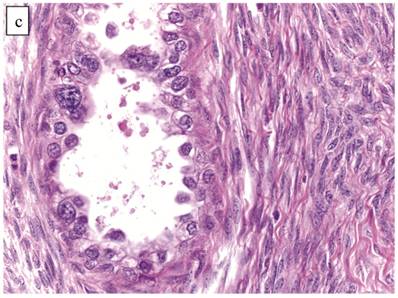

Figure 3

Carcinoma with adenofibromatous background. The carcinoma component exhibits a (A) tubulocystic pattern with (B) oxyphilic, hobnail, and flat atypical cells. (C) The adenofibromatous component does not show architectural features of clear cell carcinoma or notable atypia.

J Cancer Image J Cancer Image J Cancer Image

The background of the tumor contained variable amounts of adenofibromatous components (Fig. 3C). The proportion of the clear cell CA component in the tumors ranged from focal to diffuse, but cases with focal CA components exceeded conventional definitions for microinvasion (>3 mm in greatest dimension). Notable nuclear atypia was focally present in the adenofibromatous background in 34 (24%) cases, and the histologic appearance of such foci was similar to those with notable atypia in APTs described above. A comparison with non-adenofibromatous clear cell CAs is shown in Table 4.